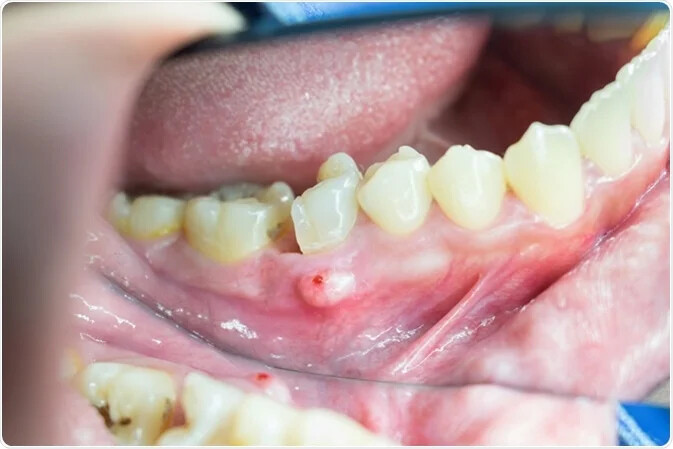

A dental abscess is your body's inflammatory reaction to an infection in the tooth's nerve. The abscess itself is a collection of pus arising from a source of infection at the tooth's root, which can break through the tissues and discharge into the mouth.

Pus and swelling of surrounding tissues

Acute apical abscess treatment starts at the source of infection. Your dental professional may need to drain the infection and deliver antibiotics if the infection has spread for large swellings. For dental abscesses contained in the mouth, your dentist may recommend root canal therapy or extraction of the infected tooth.